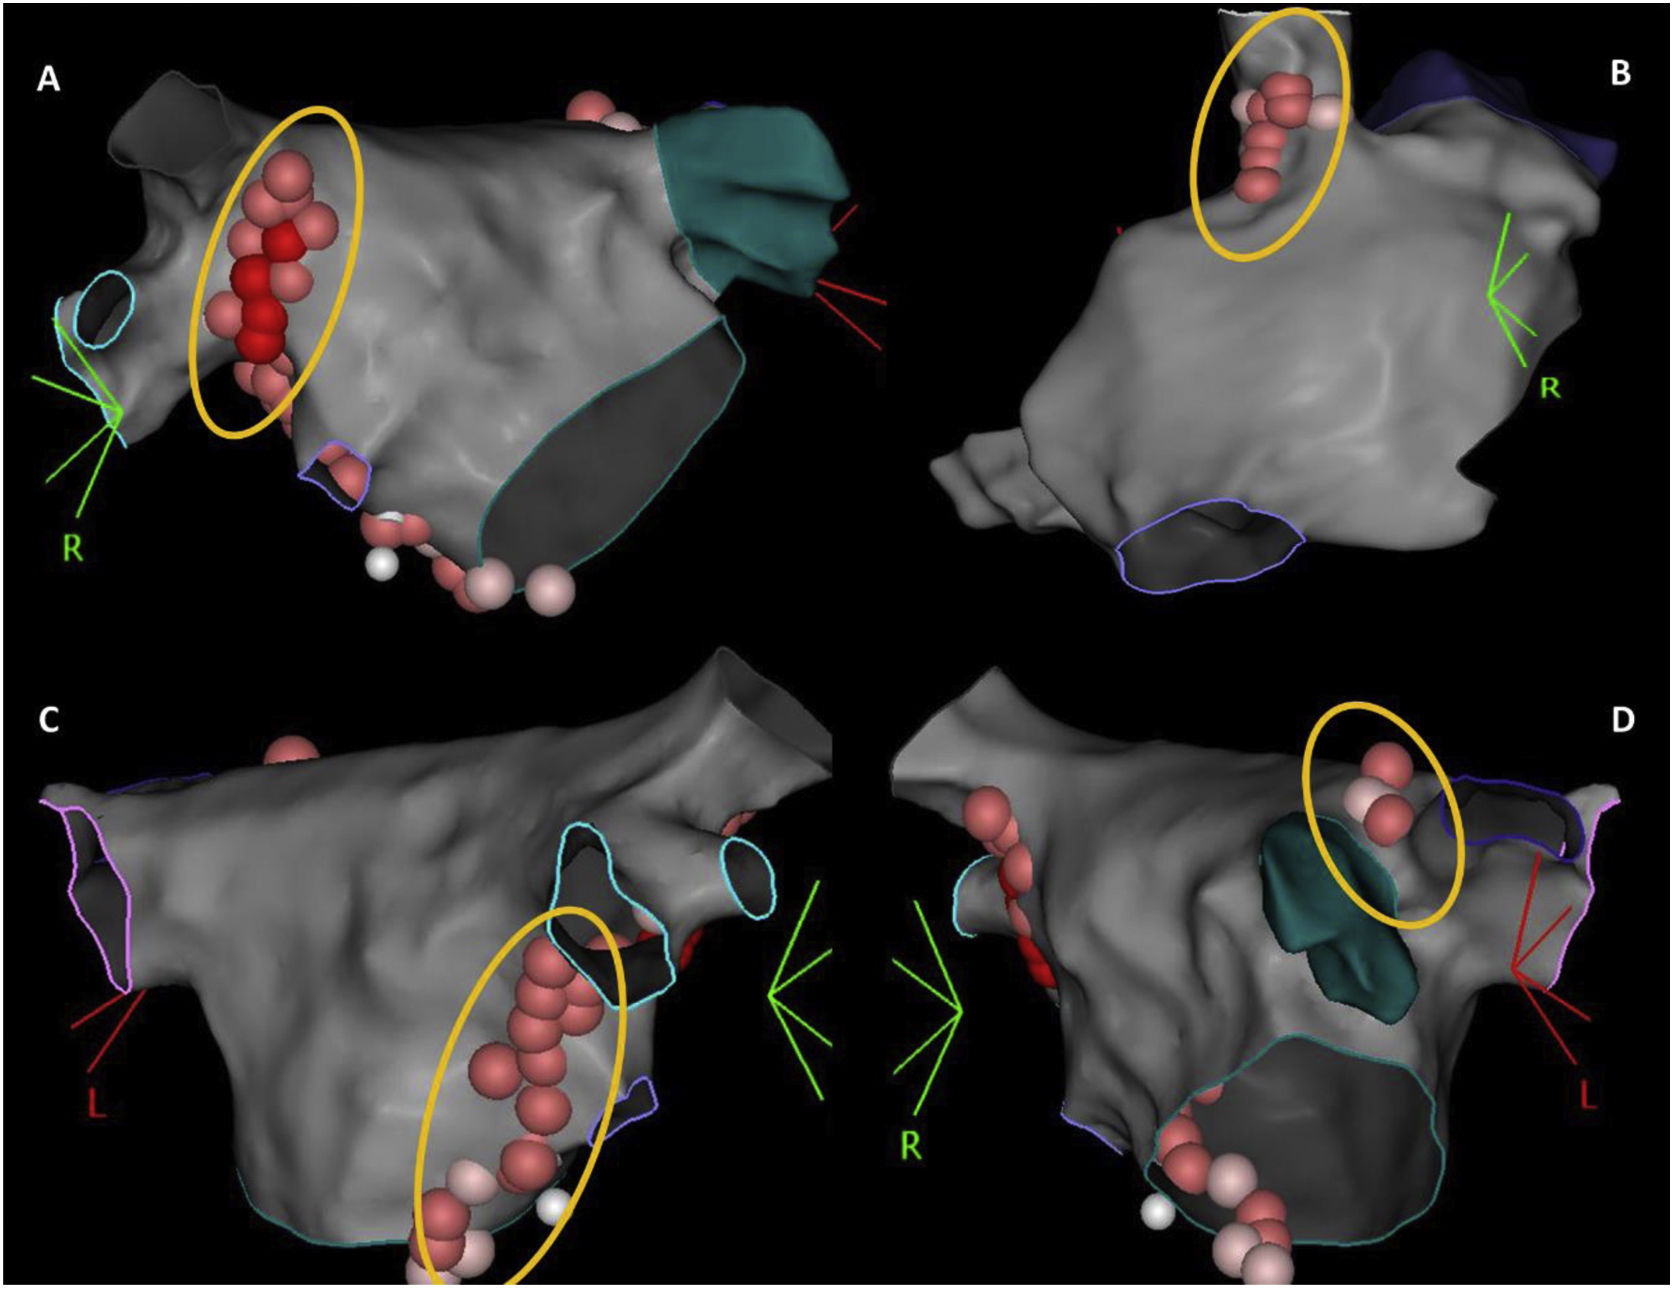

According to the type of rhythm disturbance triggered by extracardiac vagal stimulation, and also that which occurred clinically, sequential, and anatomically guided GP ablation was directed toward the ganglia most likely responsible. For patients with asystole or severe sinus bradycardia, ablation always started at the right anterior GP (RAGP), at the superoanterior area near the root of the right superior PV. If positive vagal response persisted, ablation continued, whenever necessary: (i) at the left superior GP (LSGP), located in the superolateral area around the root of the left superior PV and between the left superior PV and the left atrial appendage, and at the left lateral GP (LLGP) between the LAA and the left superior and left inferior GPs (more likely to affect AV nodal response); (ii) at the right inferior GP (RIGP) at the postero-inferior area near the root of the right inferior PV, at the postero-inferior border of the interatrial septum and posterior to the CS ostium (more likely to affect AV nodal response); (iii) at the right superior GP (RSGP) located between the superior vena cava and the aortic root just above the right superior pulmonary vein, at the postero-medial SVC-right atrial junction (more likely to affect sinus nodal response) (Figure 1). The left inferior GP area, at the infero-posterior border of the left inferior PV, was typically avoided to reduce the risk of esophageal lesion. RF ablation was performed using an irrigated catheter with contact force sensor (THERMOCOOL SMARTTOUCH™ SF Catheter) and guided by the ablation index, ranging between 380 and 500, according to the location. Extracardiac vagal stimulation was repeated after each GP group ablation to assess the degree of parasympathetic denervation. The elimination of cardiac parasympathetic response to vagal stimulation (i.e., elimination of asystole, severe bradycardia, or AV block) was the acute endpoint of the procedure.

The 3-dimensional representation of the main ganglionated plexus (GP) location. Upper panel: (A) RAGP between the right upper pulmonary vein and the right atrium; (B) RSGP between the superior vena cava and aortic root just above the right upper pulmonary vein; lower panel: (C) RIGP at the roof of the coronary sinus and medial and just under the tricuspid valve and the coronary sinus ostium; (D) LSGP at superolateral area around the root of the left superior pulmonary vein.

LSGP: left superior ganglionated plexus; RAGP: right anterior ganglionated plexus; RIGP: right inferior ganglionated plexus; RSGP: right superior ganglionated plexus.